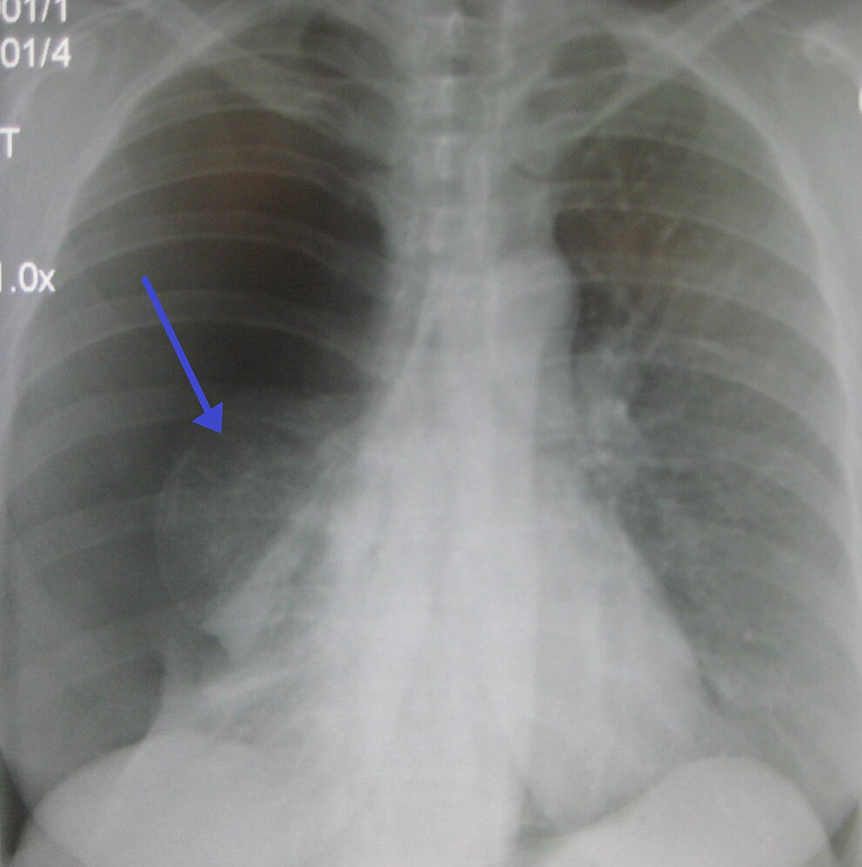

폐기흉 관련 이미지. 위키피디아

서울아산병원에 따르면 기흉은 폐에 생긴 구멍으로 공기가 새면서 늑막강 안에 공기가 차는 질환을 의미한다. 새는 공기의 양이 증가할수록 폐가 정상 기능을 하지 못한다.

흉강 안으로 유입되는 공기가 배출되지 않는 경우 양쪽 폐와 심장 사이의 공간과 심장이 한쪽으로 쏠려 응급상황이 발생할 수 있다.